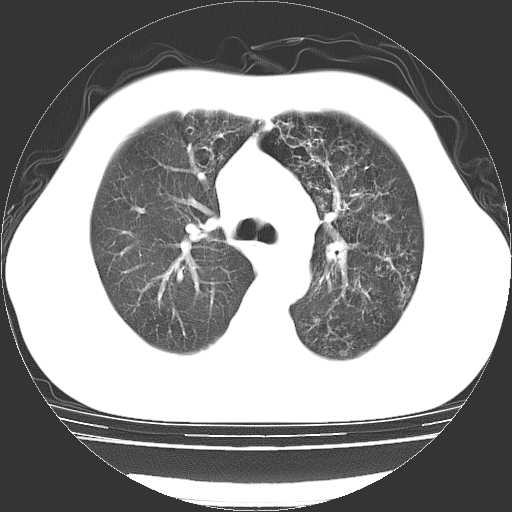

以下是引用zyx168在2006-12-4 15:30:00的发言:[br]经典!支气管肺囊肿并感染。

以下是引用dyqct在2006-12-4 17:11:00的发言:[br]典型的囊状支扩合并感染。

以下是引用liaoqiang在2006-12-4 16:12:00的发言:[br]局部肺叶内可见扩张的支气管壁,考虑为支扩。部份囊样影内有小液平和肺内散布斑片征影、小结节及纤维灶,提示支扩伴感染,且由于局部呈现有树芽征感染以结核可能性大。

以下是引用zhoucan076在2006-12-4 16:48:00的发言:[br]囊状支扩合并感染